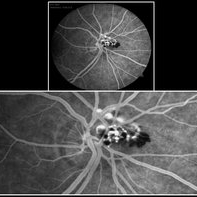

Coats' Disease

A 14-year-old male patient was admitted for visual evaluation. Visual acuity s/c in the right eye and 20/80 in the left eye. According to family members, he reported low vision since childhood. He had already undergone treatment with photocoagulation in another service to which he had a diagnostic hypothesis of Coatas disease. Laboratory tests were requested (HIV, TOXO, TOXOCARIASIS, ECA, VDRL, PPD). In the evaluation it was observed important exudation in the posterior pole, some vascular irregularities in the right eye. In the left eye, there is retinoschisis affecting the entire posterior pole and the region nasal to the optic disc, macula with a characteristic aspect of a cartwheel. Well exemplified by OCT-A (Structrure Deep: IPL - 25, OPL - 25).

Photographer: JEFFERSON R SOUSA - Study Center and Ophthalmological Research Dr. Andre M V Gomes, Institute Dr. Suel Abujamra São Paulo-Brazil

Imaging device: Topcon TRC-50 DX, Imaginet 4.0, angle de 50 graus. Flash 50w-s

Condition/keywords: Coats' disease, retinoschisis